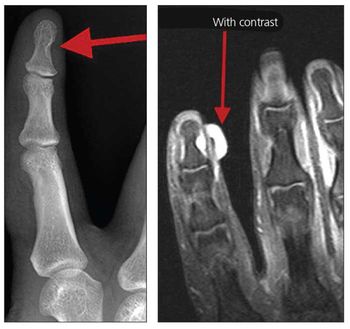

A 25-year-old man was seen in the orthopedic clinic with a complaint of severe, exquisite pain at the ulnar aspect of the distal phalanx of his dominant right index finger. The pain had been present for 10 years, but he had not sought treatment.